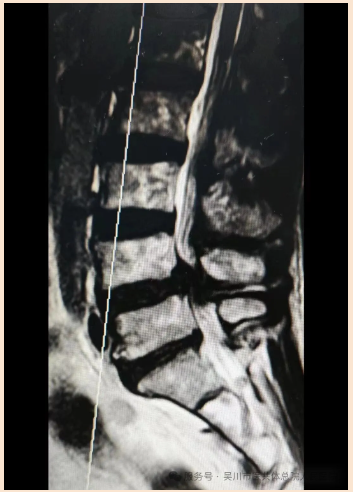

70岁的文先生被反复腰背部疼痛伴右下肢麻痛困扰1年,近期症状突然加重,严重影响生活质量,于是选择到我院骨外科三区治疗。经保守治疗效果不佳,MRI检查显示其腰4、5椎间盘向后脱出,双侧神经根及马尾受压,椎管显著狭窄,病情危急。

该科主任、主任医师曾维带领骨外科三区团队仔细研判病情,决定自主开展高难度手术。术中,医护团队精准实施 “腰椎后路椎板切除 L4、5椎管减压+ L4/5椎间盘切除椎间融合 + 腰4、5椎体椎弓根钉内固定术”,手术全程顺利。术后,文先生下肢麻痛等症状明显减轻,久违的轻松感让他对曾维团队的精湛医技赞不绝口。